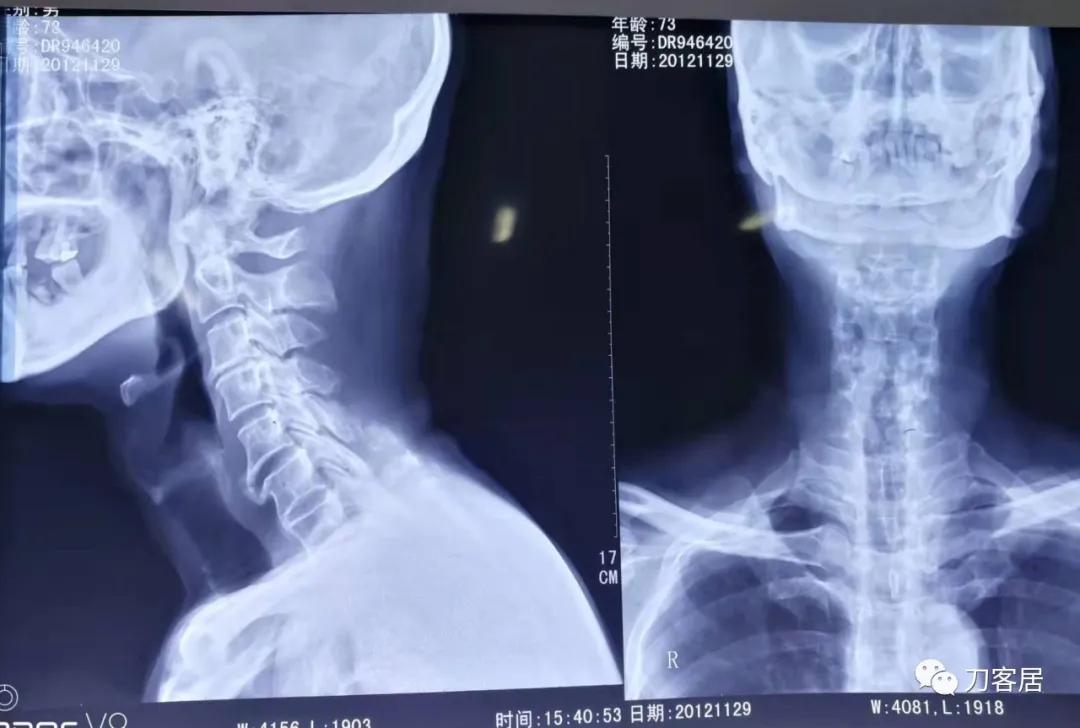

图16. 2012年11月29日颈椎管成形术前颈椎正侧位X线片,片子显示当时年龄是78岁。